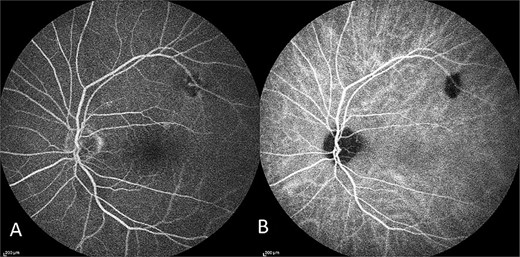

Optical coherence tomography (OCT) demonstrated an atrophied right macular. Whilst the left eye showed a thickened choroid, multiple pigment epithelial detachments (PED), subretinal fluid and intraretinal fluid nasally. This is shown in Figs 2 and 3.

OCT of left eye – showing IRF and pigment epithelial detachment.

The diagnosis of CSCR was made by the patient’s ophthalmologist, meeting diagnostic criteria as seen in Table 1. The patient meets major criteria with an OCT showing serous retinal detachment, and RPE alterations seen in Figs 2 and 3, respectively. Figure 2 displays a subfoveal choroidal thickness of 454 μm meeting the minor criteria.